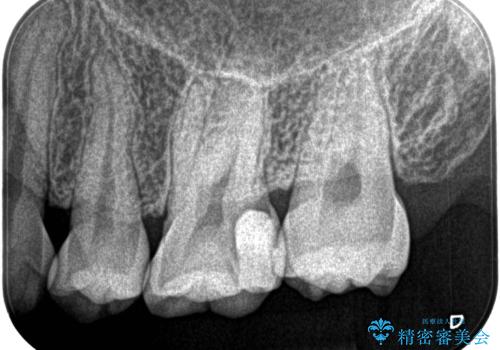

湾曲根管。精密根管治療

担当医 河口智英